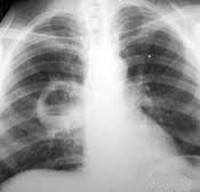

Исследование гемограммы выявляет анемию, лейкоцитоз со сдвигом формулы влево, повышение СОЭ, токсическую зернистость нейтрофилов. В моче определяется цилиндрурия, протеинурия. Для биохимических сдвигов при хроническом гнойном процессе типична гипопротеинемия, гипоальбуминемия при повышенном уровне иммуноглобулинов, гипокалиемия. Коагулопатические изменения связаны с увеличением уровня фибриногена. Решающим аргументом в постановке диагноза «хронический абсцесс» служат результаты рентгенографии легких. Типичная рентгенологическая картина - наличие в легком одной или нескольких полостей деструкции с толстыми неровными стенками и горизонтальным уровнем жидкости; вокруг гнойной полости определяются перифокальные изменения. Более детальную картину зоны патологического очага и окружающей абсцесс легочной ткани удается получить с помощью компьютерной томографии легких. Выявить деформированные бронхи и бронхоэктазы позволяет бронхография.